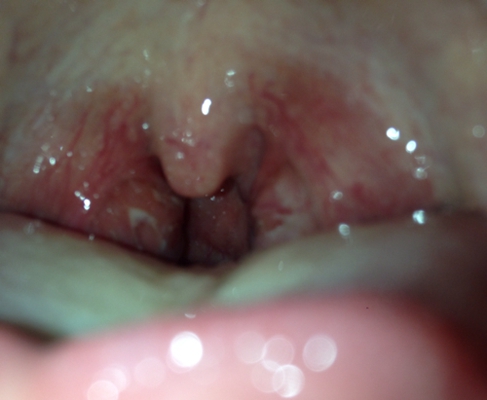

扁桃體炎圖片

扁桃體腫大